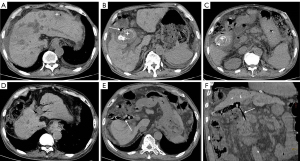

The patient presented to emergency reporting a 1-week history of continuous pain in the right middle and upper abdomen, which was aggravated for 1 day, with nausea and vomiting but no complaints of fever or shivering. The patient’s medical history showed she had a long period of cholelithiasis and gallstones, which were previously revealed on CT (Figure 1A) and were still detectable on ultrasound (US) images (Figure 1B). After hospitalization, a blood test showed an increased level of the following biomarkers: leukocyte count, 11.85×109/L; neutrophils, 83.3%; total bilirubin, 60.50 µmol/L; direct bilirubin, 26.70 µmol/L; alanine aminotransferase (ALT), 36 U/L; and aspartate transaminase (AST), 30 U/L. During hospitalization, the location of abdominal pain transferred to the lower abdomen, and the patient was unable to defecate. The physical examination (PE) showed tenderness of the whole abdomen and a positive murphy sign. A plain X-ray image showed dilated bowel loops in the middle abdomen and pneumatosis (Figure 1C). There were no detectable stones, but an accumulation of gas in the gallbladder was shown on the repeated abdominal CT (Figure 1D). Notably, the coronal CT images clearly showed the formation of a CDF (Figure 1E). In addition, a large circular stone (maximal diameter, 4.0 cm) with mixed density was detected in the small intestine, and bowel dilatation down to this level was revealed (Figure 1F), consistent with a developed CEF. Based on these findings, a definite diagnosis of CDF with a cholelithic obstruction was determined for the patient. Considering that nonoperative measures failed to alleviate the symptoms, a laparotomy was conducted. During the surgical operation, a hard mass was identified and obstructed at the distal ileum nearly 15 cm from the ileocecal area. A stone 4.0 cm × 3.0 cm in size was removed. Furthermore, the gallbladder was found to be intensely edematous and densely adhered to the surrounding tissues. Instead of the surgical resection of the gallbladder, negative pressure drainage-assisted peritoneal irrigation was conducted, and a drainage tube was placed in the pelvic cavity. Administration of intravenous fluids and antibiotics were commenced after the operation. The patient made a full recovery 10 days post-operation and was discharged. The postoperative US showed the gallbladder was not well visualized. The 1-year follow-up abdominal CT revealed gallbladder atrophy and no presence of gas either in the gallbladder or the biliary tract (Figure 1G).